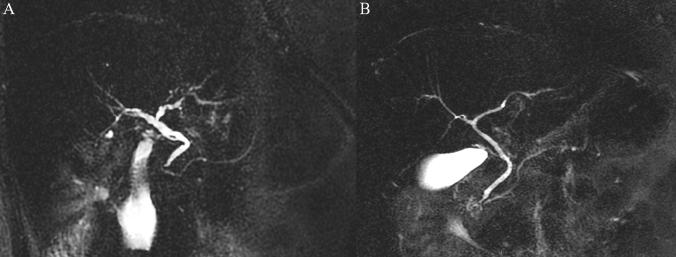

To evaluate the potential variability of Manganese (Mn) in commercial pineapple juice (PJ) produced in different years and to identify the optimal Mn concentration in the correct amount of PJ to be administered prior to Magnetic Resonance Cholangiopancreatography (MRCP) in order to suppress the gastroduodenal (GD) liquid signal. The Mn concentration in PJ produced in different years was defined using Atomic Absorption Spectrometry. The optimal Mn concentration and the amount of PJ, were estimated in an in-vitro analysis, and were then prospectively tested in a population of patients who underwent MRCP. The results were compared with those achieved with the previous standard amount of PJ used in a similar population. The concentrations of Mn in commercial PJ produced in different years did not differ. A total amount of 150 ml (one glass) of PJ having a high Mn content (2.37 mg/dl) was sufficient for the suppression of the GD liquid signal, despite the additional dilution caused by GD liquids since it led to a final concentration of Mn of 0.5-1.00 mg/dl. The optimized single-dose oral administration of 150 ml (approximately one glass) of PJ having a high Mn concentration prior to MRCP was adequate to guarantee the correct amount of Mn to suppress the GD signal.

为了评估不同年份生产的商业菠萝汁(PJ)中锰(Mn)的潜在变异性,并确定在磁共振胰胆管造影(MRCP)前给予适量 PJ 以抑制胃十二指肠(GD)液体信号的最佳 Mn 浓度。使用原子吸收光谱法定义了不同年份生产的 PJ 中的 Mn 浓度。在体外分析中估算了最佳 Mn 浓度和 PJ 量,然后在接受 MRCP 的患者人群中进行了前瞻性测试。结果与在类似人群中使用先前标准量的 PJ 获得的结果进行了比较。不同年份生产的商业 PJ 中的 Mn 浓度没有差异。尽管由于 GD 液体引起的额外稀释,150 毫升(一杯)具有高 Mn 含量(2.37 毫克/分升)的 PJ 总量足以抑制 GD 液体信号,但最终 Mn 浓度为 0.5-1.00 毫克/分升。在 MRCP 前给予 150 毫升(约一杯)高浓度 Mn 的 PJ 的优化单次口服给药足以保证抑制 GD 信号的正确 Mn 量。